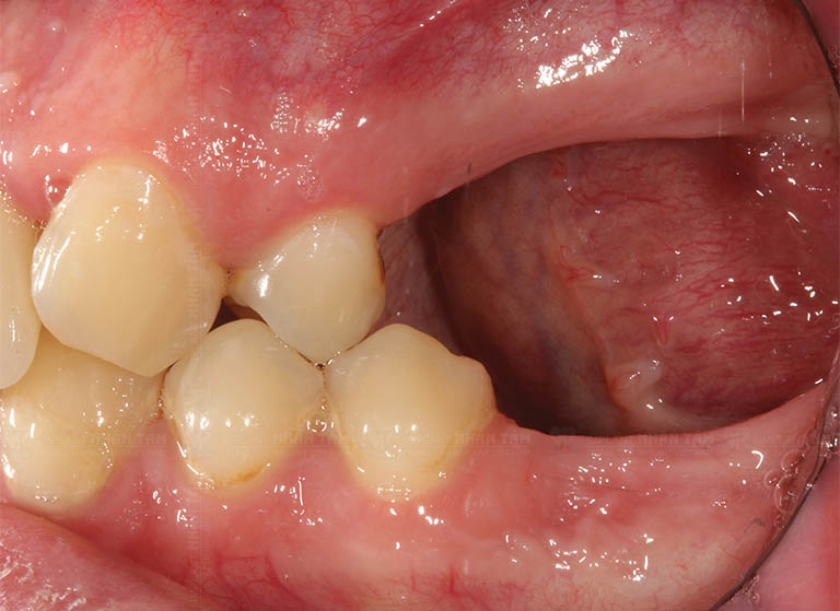

Một trong những hệ lụy lớn nhất của việc không trồng răng sau khi mất là tình trạng tiêu xương hàm. Khi không còn răng, xương hàm không nhận được áp lực cần thiết trong quá trình nhai, dẫn đến việc xương dần dần bị tiêu biến. Điều này không chỉ làm giảm mật độ xương mà còn có thể làm cho khuôn mặt trở nên hóp lại, mất đi vẻ đầy đặn và trẻ trung.

Hình ảnh tình trạng tiêu xương hàm khi bị mất răng

Mất răng lâu năm cũng có thể dẫn đến tụt lợi, làm lộ chân răng và tạo điều kiện cho vi khuẩn phát triển. Tình trạng này không chỉ gây ra các vấn đề về vệ sinh răng miệng mà còn làm tăng nguy cơ mắc các bệnh nướu, có thể dẫn đến mất thêm răng. Khi lợi tụt, người bệnh có thể gặp khó khăn trong việc giữ gìn vệ sinh răng miệng, từ đó ảnh hưởng đến sức khỏe tổng thể.

Khi một răng bị mất, các răng lân cận có thể bị dịch chuyển để lấp đầy khoảng trống, dẫn đến tình trạng lệch lạc trong hàm. Sự dịch chuyển này không chỉ làm mất đi sự cân đối mà còn gây áp lực không cần thiết lên các răng khác, dễ dẫn đến sâu răng và các vấn đề khác liên quan đến sức khỏe răng miệng.